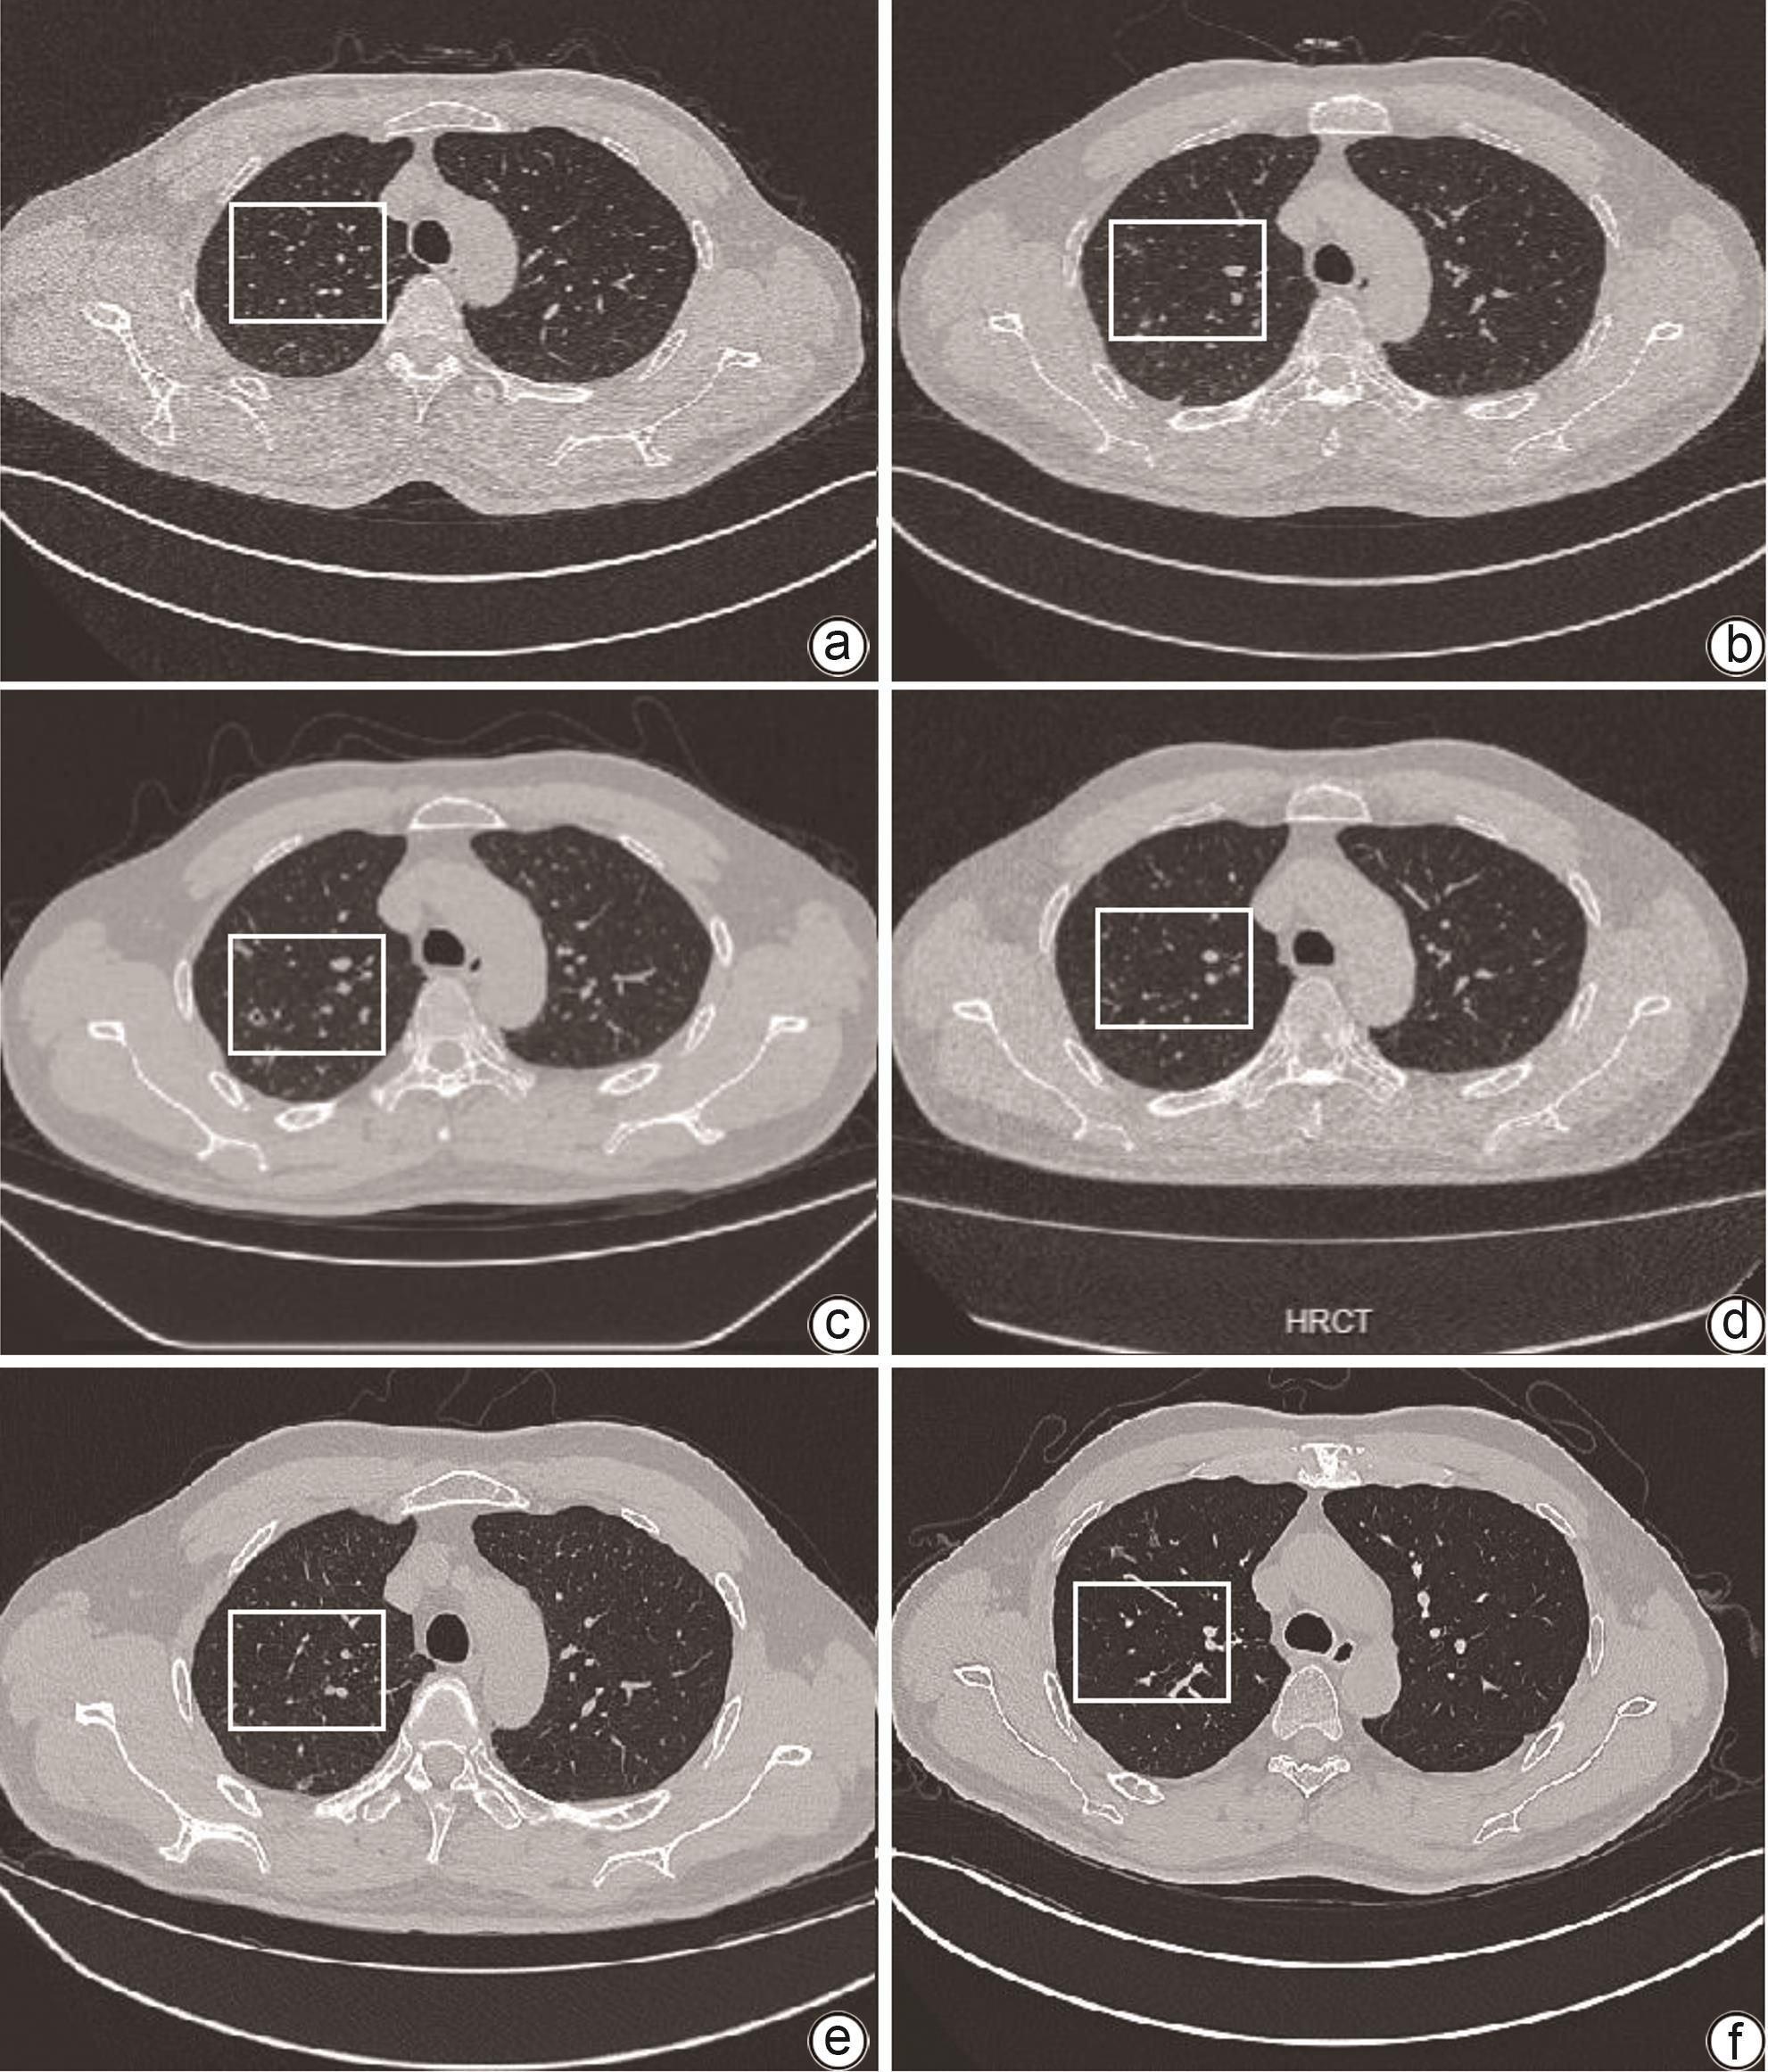

摘要: 自身免疫性肝病重叠综合征表现为患者出现一种以上的自身免疫性肝病的生化、免疫、组织学或胆管造影特征,常需联合使用免疫抑制剂治疗。肺隐球菌病是一种由新型隐球菌或格特隐球菌引起的侵袭性肺真菌病,易在免疫功能低下患者中发生。本病例为1例重叠综合征,在免疫抑制治疗过程中发现并治疗肺隐球菌病,在抗真菌治疗过程中肝功能出现异常,根据患者的肝功能情况,评估了更换抗真菌药物的可行性,综合考虑后制定了在密切监测肝功能的情况下,积极治疗新型隐球菌感染的治疗策略,避免了感染的进展。提示在启动免疫抑制治疗前,除了全面评估全身感染灶,对于可疑感染灶也必须保持监测。Abstract: Patients with overlap syndrome (OS) of autoimmune liver disease may present with more than one biochemical, immunological, histological or cholangiography features of autoimmune liver disease (AILD) and often require a combination of immunosuppressants for treatment. Pulmonary cryptococcosis is a type of invasive pneumomycosis caused by Cryptococcus neoformans or Cryptococcus gattii and has a relatively high incidence rate in immunocompromised patients. This case report presents a patient with OS who was found to have pulmonary cryptococcosis during immunosuppressive therapy and developed abnormal liver function during antifungal treatment. Based on the liver function of the patient, the feasibility of adjusting antifungal agents was assessed, and active treatment strategies for novel cryptococcal infection were developed under the close monitoring of liver function, which helped to avoid the progression of infection. It is suggested that before the initiation of immunosuppressive therapy, systemic foci of infection should be comprehensively evaluated, and suspicious foci of infection should be monitored continuously.

[1] CZAJA AJ, CARPENTER HA. Autoimmune hepatitis overlap syndromes and liver pathology[J]. Gastroenterol Clin North Am, 2017, 46( 2): 345- 364. DOI: 10.1016/j.gtc.2017.01.008. [2] SILVEIRA MG, TALWALKAR JA, ANGULO P, et al. Overlap of autoimmune hepatitis and primary biliary cirrhosis: long-term outcomes[J]. Am J Gastroenterol, 2007, 102( 6): 1244- 1250. DOI: 10.1111/j.1572-0241.2007.01136.x. [3] JIANG Y, XU BH, RODGERS B, et al. Characteristics and inpatient outcomes of primary biliary cholangitis and autoimmune hepatitis overlap syndrome[J]. J Clin Transl Hepatol, 2021, 9( 3): 392- 398. DOI: 10.14218/JCTH.2021.00008. [4] CHALIFOUX SL, KONYN PG, CHOI G, et al. Extrahepatic manifestations of primary biliary cholangitis[J]. Gut Liver, 2017, 11( 6): 771- 780. DOI: 10.5009/gnl16365. [5] GRAVERSGAARD C, SALMON JE, SCHREIBER K. First prospective observational data on pregnancies in patients with primary Sjögren’s syndrome[J]. Lancet Rheumatol, 2023, 5( 6): e306- e307. DOI: 10.1016/S2665-9913(23)00123-6. [6] CHAZOUILLÈRES O, WENDUM D, SERFATY L, et al. Primary biliary cirrhosis-autoimmune hepatitis overlap syndrome: clinical features and response to therapy[J]. Hepatology, 1998, 28( 2): 296- 301. DOI: 10.1002/hep.510280203. [7] Chinese Society of Hepatology, Chinese Medical Association. Guidelines on the diagnosis and management of primary biliary cholangitis(2021)[J]. J Clin Hepatol, 2022, 38( 1): 35- 41.中华医学会肝病学分会. 原发性胆汁性胆管炎的诊断和治疗指南(2021)[J]. 临床肝胆病杂志, 2022, 38( 1): 35- 41. [8] MA L, GAO LL. Diagnosis and treatment of patients with primary biliary cholangitis-autoimmune hepatitis overlap syndrome[J]. J Prac Hepatol, 2023, 26( 2): 301- 304. DOI: 10.3969/j.issn.1672-5069.2023.02.038.马莉, 高丽丽. 原发性胆汁性胆管炎-自身免疫性肝炎重叠综合征诊治进展[J]. 实用肝脏病杂志, 2023, 26( 2): 301- 304. DOI: 10.3969/j.issn.1672-5069.2023.02.038. [9] Chinese Society of Hepatology, Chinese Medical Association. Guidelines on the diagnosis and management of autoimmune hepatitis(2021)[J]. J Clin Hepatol, 2022, 38( 1): 42- 49.中华医学会肝病学分会. 自身免疫性肝炎诊断和治疗指南(2021)[J]. 临床肝胆病杂志, 2022, 38( 1): 42- 49. [10] FREEDMAN BL, DANFORD CJ, PATWARDHAN V, et al. Treatment of overlap syndromes in autoimmune liver disease: a systematic review and Meta-analysis[J]. J Clin Med, 2020, 9( 5): 1449. DOI: 10.3390/jcm9051449. [11] YI L, TAO YH, CHEN ZY, et al. Study on the clinical features and CT findings of pulmonary Cryptococcosis in immunocompetent patient[J]. J Clin Radiol, 2023, 42( 1): 51- 55.易黎, 陶雅红, 陈智勇, 等. 免疫功能正常者肺隐球菌病临床表现及CT特征分析[J]. 临床放射学杂志, 2023, 42( 1): 51- 55. [12] KOHNO S, KAKEYA H, IZUMIKAWA K, et al. Clinical features of pulmonary cryptococcosis in non-HIV patients in Japan[J]. J Infect Chemother, 2015, 21( 1): 23- 30. DOI: 10.1016/j.jiac.2014.08.025. [13] SONG KD, LEE KS, CHUNG MP, et al. Pulmonary cryptococcosis: imaging findings in 23 non-AIDS patients[J]. Korean J Radiol, 2010, 11( 4): 407- 416. DOI: 10.3348/kjr.2010.11.4.407. [14] MA LL, RAO HL, TANG F, et al. Analysis of CT imaging features and clinical pathological features in patients with pulmonary cryptococcosis[J]. Clin J Med Offic, 2022, 50( 12): 1310- 1312, 1316. DOI: 10.16680/j.1671-3826.2022.12.30.马利利, 饶会林, 唐飞, 等. 肺隐球菌病患者肺部CT影像学表现及临床病理特征分析[J]. 临床军医杂志, 2022, 50( 12): 1310- 1312, 1316. DOI: 10.16680/j.1671-3826.2022.12.30. [15] VISNEGARWALA F, GRAVISS EA, LACKE CE, et al. Acute respiratory failure associated with cryptococcosis in patients with AIDS: analysis of predictive factors[J]. Clin Infect Dis, 1998, 27( 5): 1231- 1237. DOI: 10.1086/514984. [16] CHAI CY, WANG T. Clinical analysis of pulmonary cryptococcus infection in the elderly and literature review[J]. Clin Misdiagn Misther, 2023, 36( 2): 1- 4, 10. DOI: 10.3969/j.issn.1002-3429.2023.02.001.柴春艳, 王婷. 老年肺隐球菌感染临床分析并文献复习[J]. 临床误诊误治, 2023, 36( 2): 1- 4, 10. DOI: 10.3969/j.issn.1002-3429.2023.02.001. [17] HOWARD-JONES AR, SPARKS R, PHAM D, et al. Pulmonary cryptococcosis[J]. J Fungi(Basel), 2022, 8( 11): 1156. DOI: 10.3390/jof8111156. -